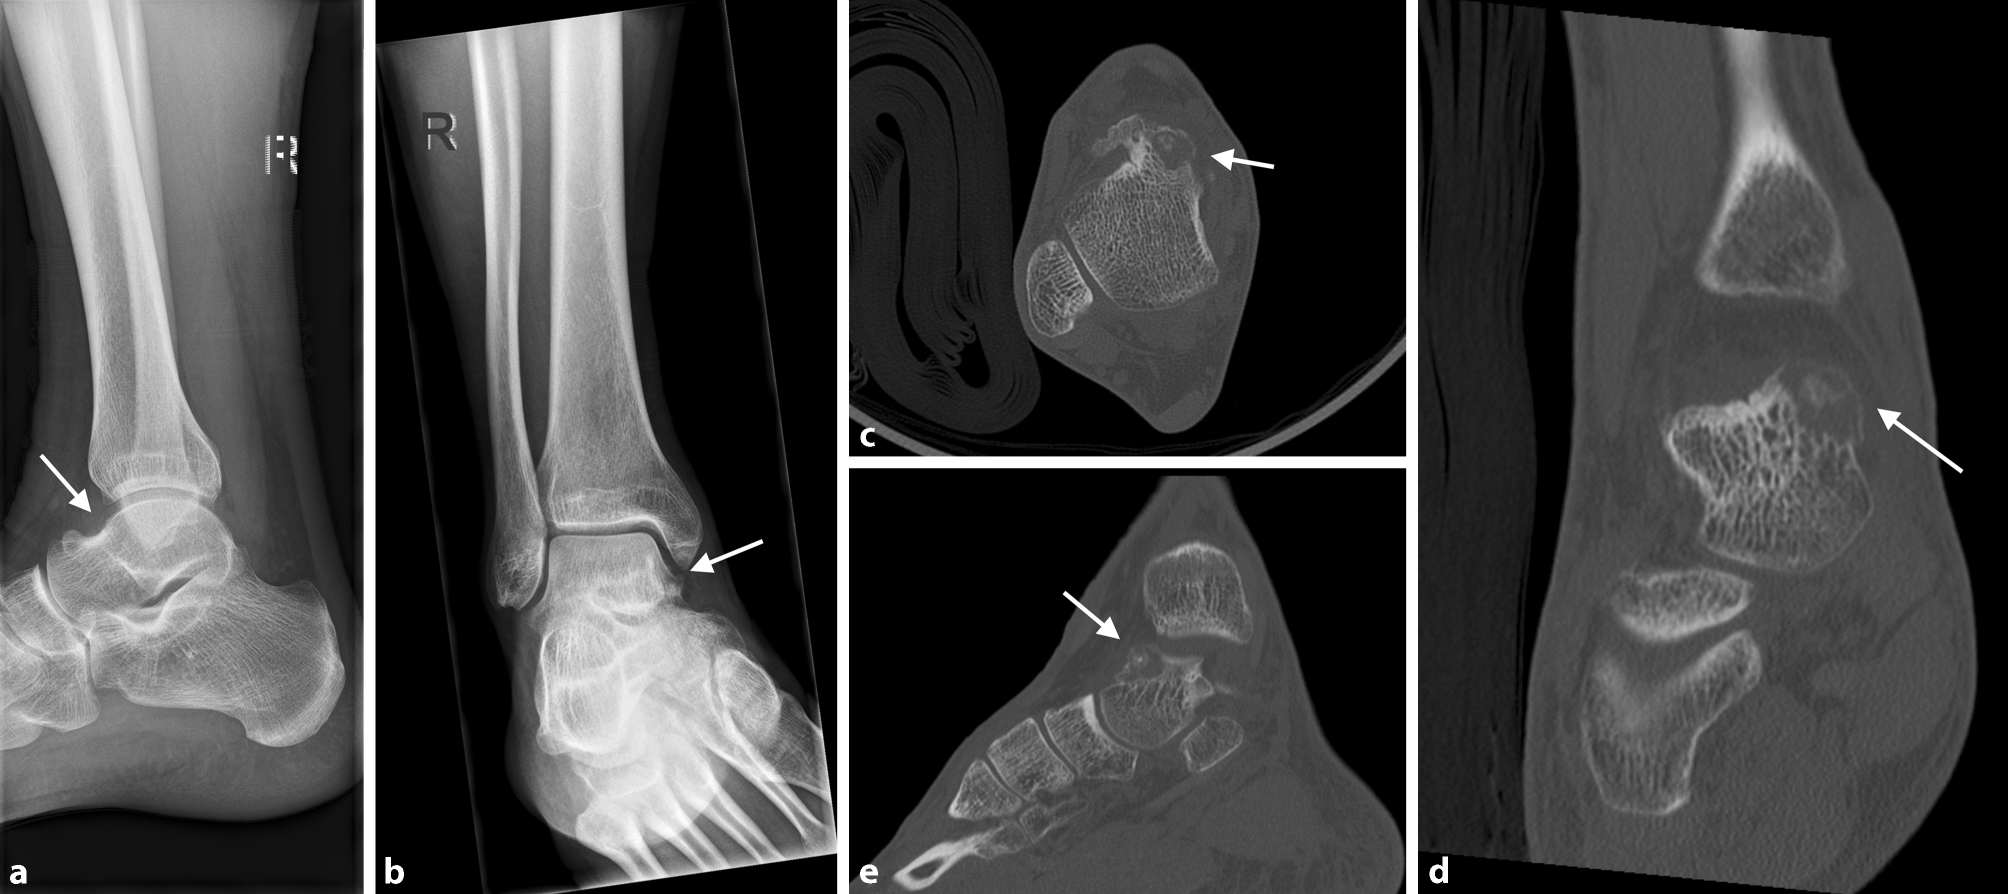

Fig. 2

ab 18-year-old male patient with osteoid osteoma located in the talar neck of the right foot adjacent to the medial talar shoulder, presenting as blurred, lucent region on the anteroposterior (ap) (a) and lateral (b) view (arrows pointing at the regions of interest). ce Transverse (c), frontal (d) and sagittal (e) CT scans showing osteolytic lesion with cortical thinning and central sclerosis in the medial aspect of the talar neck (arrows pointing at the regions of interest)